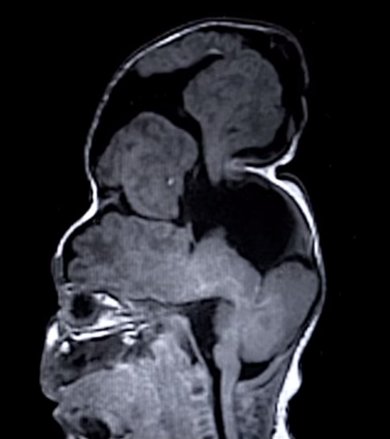

انسفالوسل (encephalocele) نوعی بیماری مادرزادی است که به سبب تشکیل ناقص سلولهای عصبی جنین بروز میکند.

در این بیماری بخشهایی از مغز به صورت برآمدگی، از طریق روزنههای جمجمه بیرون زده و پوست و یا غشاء نازکی روی آن را میپوشاند.

پزشکان برای انجام این عمل جراحی از مدلهای چاپ سه بعدی استفاده کردند. 100 سانتی متر مکعب از مغز بنتلی خارج از جمجمه وی شکل گرفته بود، به طوری که جراحان ناچار به گسترش جمجمه او شدند. آنها قبل از انجام این عمل جراحی از یک مدل پلاستیکی استفاده کردند تا نتیجه این عمل را پیش بینی کنند و دریابند که چه میزان از مغز را میتوان در جمجمه جای داد.